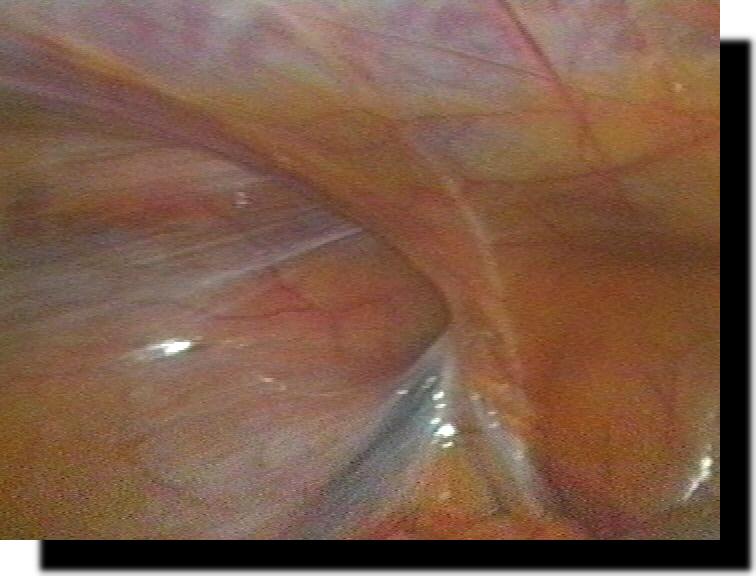

mediale Leistenhernie

indirekte Leistenhernie

laterale Leistenhernie

Spieghel´sche Hernie

Z.n. TEPP Hernioplastik mit Prolene-Netz

Rezidiv-Hernie nach endoskopischer Hernioplastik

Z.n. TEPP-Hernioplastik mit Prolene-Netz